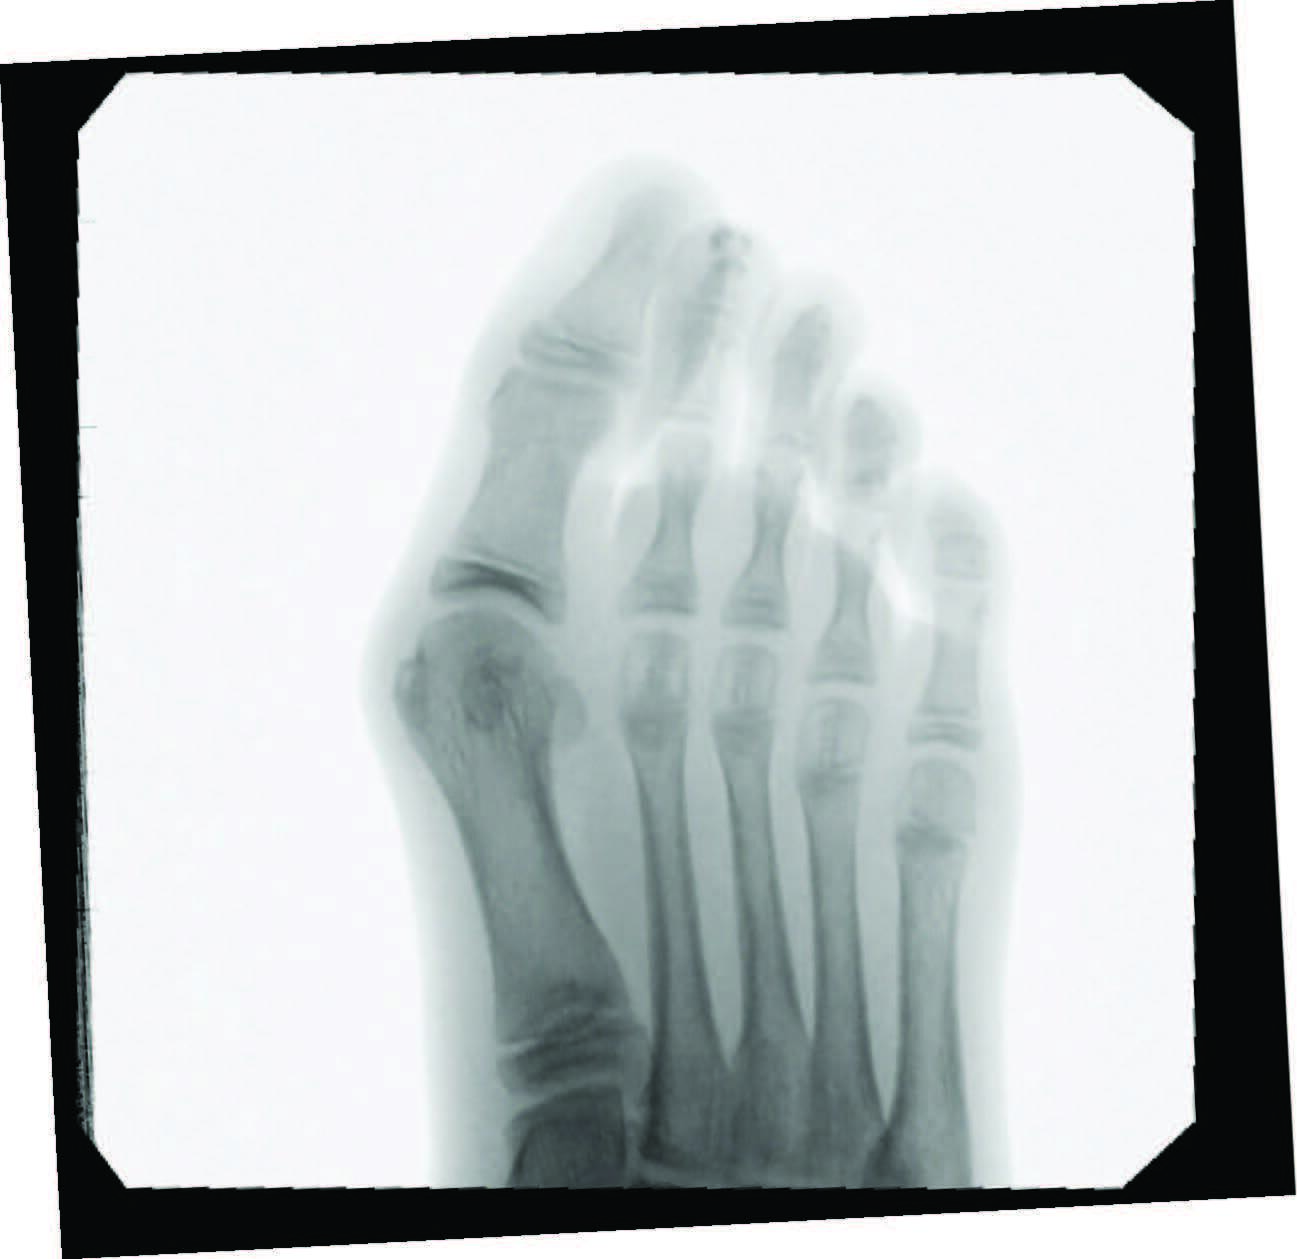

A sequential examination from hindfoot to forefoot is crucial to assess the stability of the triplanar deformity and contributing etiology. Evaluating the suppleness of the subtalar joint and Achilles tendon clinically, through range of motion, and radiographically, by measuring the talocalcaneal angle and amount of calcaneal positioning in the frontal plane, is an important first step. In Root’s theory of subtalar joint neutral, pes valgus leads to a progressive inversion of the first metatarsal relative to the hallux during the propulsive period of the stance phase in gait.3 This forefoot instability progresses MTPJ joint subluxation with the hallux tracking laterally. Forefoot evaluation includes assessing the dorsal and plantar deviation of the first tarsometatarsal joint and the flexibility of the first metatarsal joint and hallux deviation, all while the subtalar joint is in neutral.3

Predictors of juvenile HAV severity, in addition to subtalar joint pronation, include: rounding of the first metatarsal head; an atavistic cuneiform; a hypermobile or long first ray; and a high metatarsus primus adductus angle.4 Additional pes planus-related radiographic measurements include an increased first intermetatarsal angle, reported in 26.6 percent of adolescents and an increased metatarsus primus varus angle in 8.1 percent.5 Anatomic abnormalities such as Achilles equinus contractures, digital contractures, syndactyly, metatarsus adductus, hereditary exostoses, and congenital hip dislocation may need attention for long-term successful HAV treatment. Other considerations include brachymetatarsia, where a shortened lesser metatarsal leads to an abnormal transverse metatarsal parabola, allowing more lateral deviation of the hallux and increased metatarsus varus angle due to soft tissue balancing effects.

When we approach surgical correction of hallux valgus, goals include realigning the hallux joint across all three planes, improving the first intermetatarsal angle, restoring and maintaining a pain-free joint, improving cosmesis, and allowing a return to comfortable shoes. Inclusion criteria for surgery that we consider include intact vasculature, Vitamin D-25 levels above 40 nmol/dl, and medical stability in the presence of comorbidities. Percutaneous hallux valgus correction has indication for spastic or non-spastic bunions, revisions, and a wide range of intermetarsal angles. Other exclusion considerations include patients with severe osteoarthritis or osteomyelitis near the first metatarsophalangeal joint.